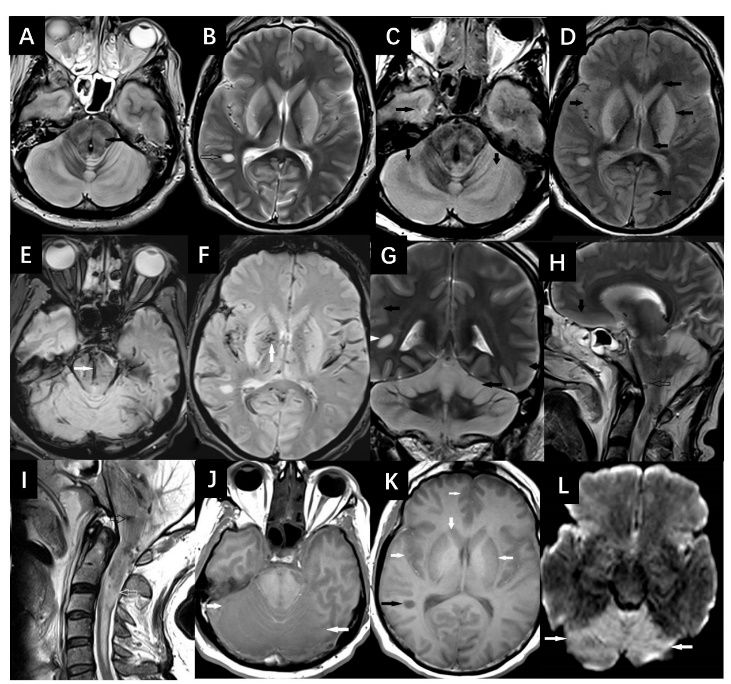

图2 一名60岁男性患者,异丙醇中毒入院后6天头颅MRI影像结果[3]

T2(A和B)和FLAIR(C和D)显示大脑和小脑皮层、白质、基底节、丘脑和双侧脑干(实心黑色箭头)呈高信号改变,右侧颞叶周围白质(B,黑边箭头)存在局灶性高信号病变;T2 *(E和F)图像显示双侧脑干和基底节区存在出血(实心白色箭头);T2冠状位(G)和矢状位(H)图像显示小脑皮质和脑干高信号改变(G和H,实心黑色箭头),右侧颞叶白质局灶性高信号病变(G,实心白色箭头),脑干存在局灶性出血(H,黑边箭头);颈髓T2影像显示颈脊髓肿胀,内部呈高信号改变(I,白边箭头);大脑(J和K)T1平扫显示大脑和小脑皮质、白质、基底节、丘脑和脑干呈双侧低信号改变(J和K,实心白色箭头)),右侧颞叶白质局灶性低信号病变(K,实心黑色箭头); DWI影像可见双侧小脑弥散受限(L,实心白色箭头)。